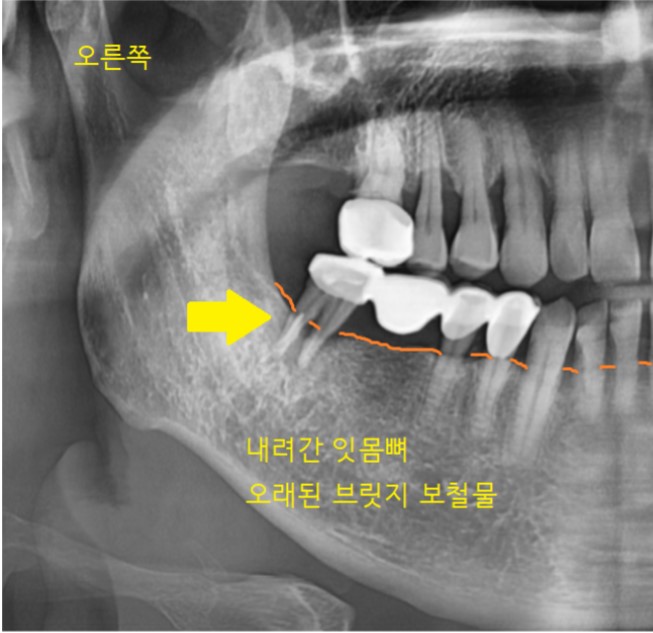

사진 속 화살표 치아를 주목해 주세요.

브릿지 치료가 되어있네요.

오래 쓰시더니 문제가 생겼습니다.

오래된 브릿지 보철의 제거가 필요해 보입니다.

정상적인 잇몸뼈는 치아머리 부위까지

채워져 있어야 합니다.

잇몸뼈가 많이 내려가서

치아를 붙잡고 있는 게 없다 보니

흔들흔들했는데요.